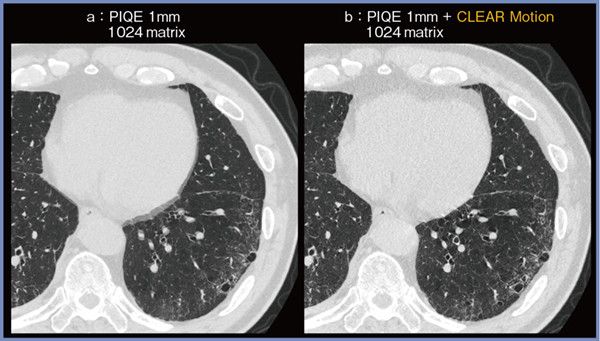

症例4は60歳代,男性,間質性肺炎の症例である。通常のPIQEの画像(図5 a)は心拍動によって心臓や気管支,血管のブレを認めるが,CLEAR Motionを適用した画像(b)ではブレが軽減され,下肺野の網状影やすりガラス影が評価しやすくなっている。

図5 例4:間質性肺炎症例へのCLEAR Motionの適用